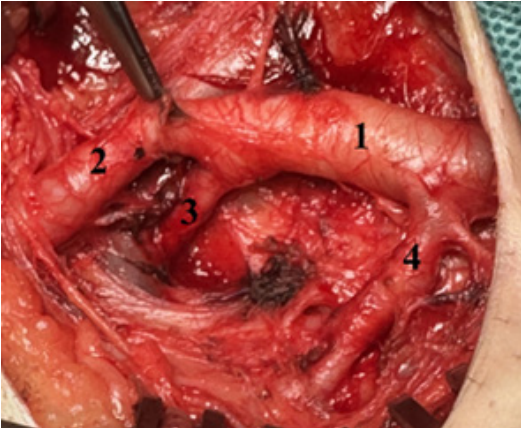

Данный клинический случай представляет отдельный интерес. Военнослужащий получил множественное осколочное ранение латеральной поверхности бедра. В проекции поражения нет магистральных сосудов. Через 21 день, во время натуживания у пациента отмечено струйное кровотечение из указанных ран. По данным УЗИ выявлена гигантская псевдоаневризма в проекции терминальных ветвей глубокой бедренной артерии на задне-медиальной поверхности бедра диаметром до 12 см.

Интраоперационно выделены артерии в паховой области. При этом во время ревизии обнаружена "находка" — крупная дополнительная артериальная ветвь, отходящая от общей бедренной артерии, идущая на латеральную поверхность бедра. Данная особенность не влияла на ход операции (рис. 5).

После введения 5 тыс. единиц нефракционированного гепарина внутривенно струйно указанные артерии пережаты. Ткани в проекции псевдоаневризмы рассечены, из ее полости удалены тромботические массы объемом до 500 мл (рис. 6).

Затем визуализирована и лигирована терминальная ветвь глубокой бедренной артерии. Послеоперационный период протекал без особенностей.

Рис. 5. Артерии паховой области с дополнительной латеральной ветвью общей бедренной артерии

Примечание: 1 — общая бедренная артерия, 2 — поверхностная бедренная артерия, 3 — глубокая бедренная артерия, 4 — дополнительная латеральная ветвь общей бедренной артерии.

Рис. 6. Оперативное лечение псевдоаневризмы терминальной ветви глубокой бедренной артерии.

Примечание: К1 — раны латеральной поверхности бедра в стадии рубцевания; К2 — проекция псевдоаневризмы; К3 — ультразвуковой снимок псевдоаневризмы глубокой бедренной артерии; К4 — удаленные тромботические массы из полости аневризмы.